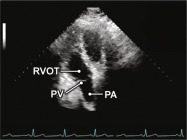

| 2.5. Mặt cắt trục dài cạnh ức qua đường ra thất phải |

||||||||

|

|

Cửa sổ siêu âm cạnh ức

Mặt cắt trục dài cạnh ức Ngửa và xoay đầu dò về phía đường ra thất phải/ |

Đường ra thất phải (RVOT) Van động mạch phổi (PV) Động mạch phổi (PA) |

|||||